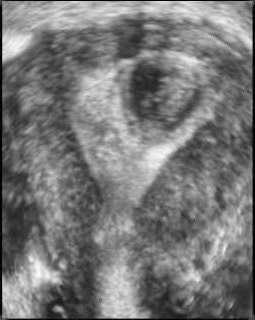

| Three-dimensional ultrasound images showing septate uteri. Images courtesy of Dr. Beryl Benacerraf. |

Foremost among these is the coronal view of the uterus, an only-in-3D image that can much more definitively distinguish the bicornuate from the septate from the unicornuate uterus.

"These kinds of images are incredibly important, particularly for the infertility patient," said Benacerraf, noting that women with septate uteri are at much higher risk for miscarriage, preterm labor, and other adverse effects.

With 3D, the sonographer can also measure the width and the depth of the septum, Benacerraf said, "which will be a very good guide for the surgeon who is going to be resecting the septum."